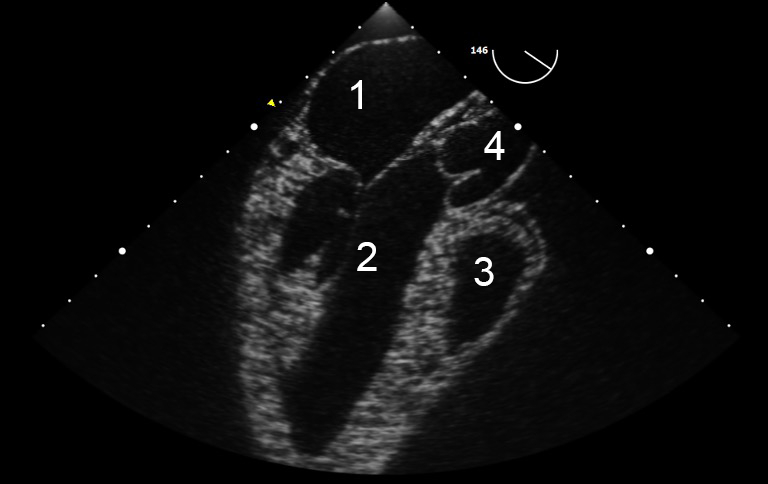

TEE Resus Mid-esophageal Long Axis 2 IU Image

Left Atrium

Left Ventricle

Right Ventricle

Aorta